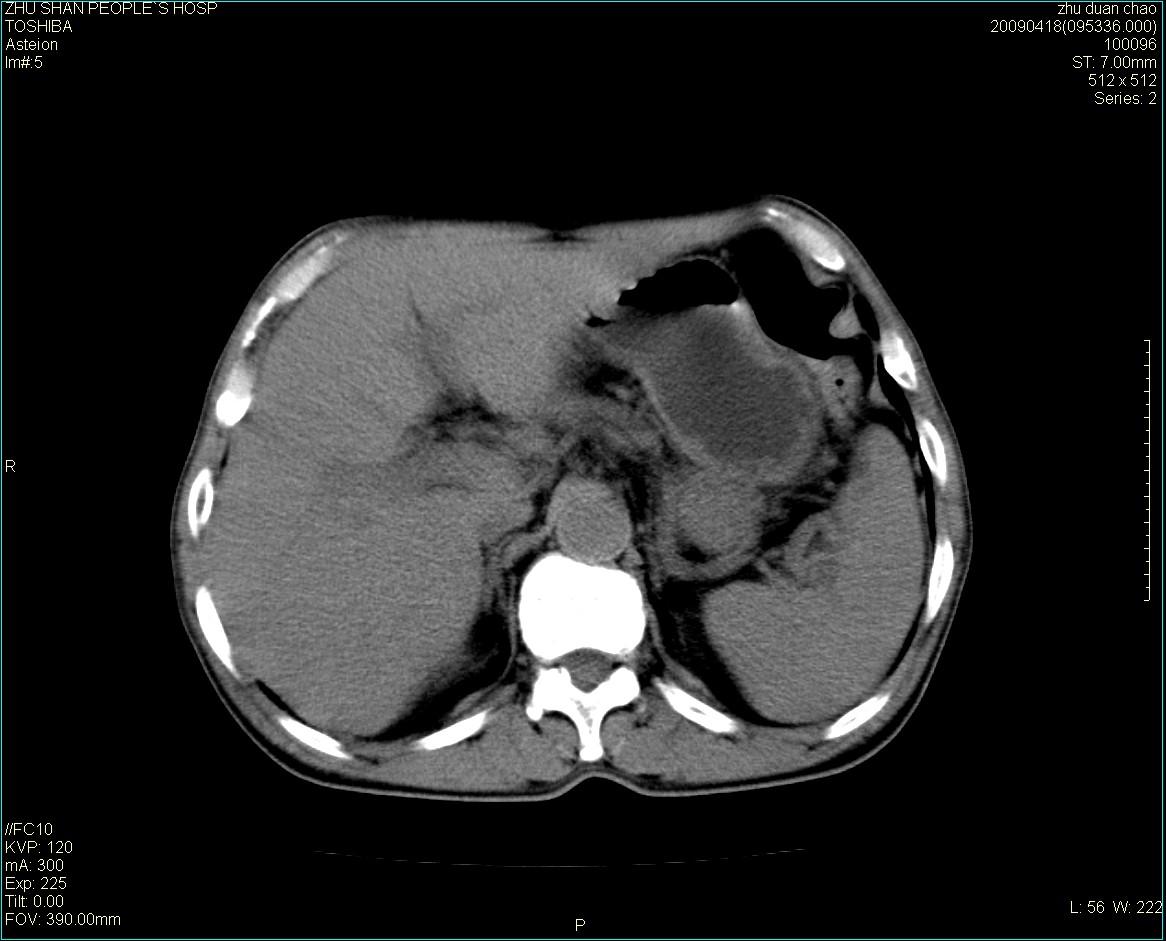

以下是引用余辉在2009-4-22 10:48:00的发言:[br]结肠肝曲附近肠段包块,病灶密度不均匀,周围肠系膜脂肪混浊,见多枚淋巴结肿大,考虑结肠癌可能性大,病灶累及范围较广建议进一步检查除外其他

以下是引用随光逐影在2009-4-22 11:57:00的发言:[br]考虑肠道肿瘤(间质瘤?)可能性大。

以下是引用ydx_74在2009-4-22 14:39:00的发言:[br]结肠癌周围侵犯可能,不能完全除外炎性病变